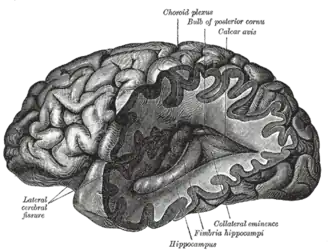

A brain–computer interface (BCI), sometimes called a brain–machine interface (BMI), is a direct communication link between the brain's electrical activity and an external device, most commonly a computer or robotic limb. BCIs are often directed at researching, mapping, assisting, augmenting, or repairing human cognitive or sensory-motor functions.[1] They are often conceptualized as a human–machine interface that skips the intermediary of moving body parts (e.g. hands or feet). BCI implementations range from non-invasive (EEG, MEG, MRI) and partially invasive (ECoG and endovascular) to invasive (microelectrode array), based on how physically close electrodes are to brain tissue.[2]